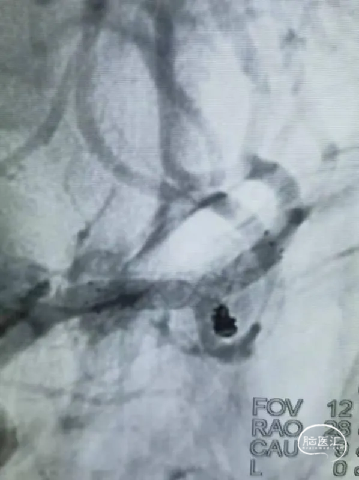

术前影像

栓塞过程

栓塞微导管精准塑形后,前推顺利到位,依次填塞三枚Jasper®SS弹簧圈。瘤颈处有壶腹,为增加弹簧圈稳定性,降低动脉瘤复发率,释放支架,复查造影,动脉瘤填塞致密,载瘤动脉通畅良好。

术后即刻影像